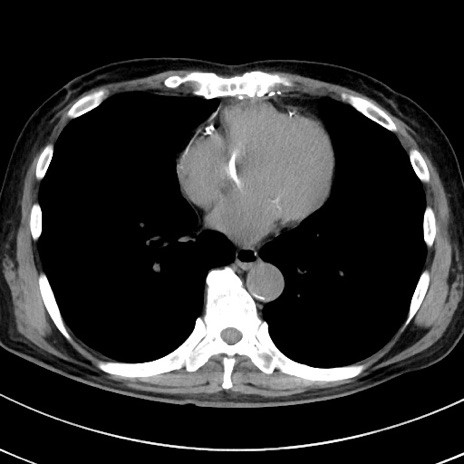

症例38(横断像)

症例

【症例】70歳代 男性

【主訴】腹痛・嘔吐

【現病歴】昨晩より、嘔吐・腹痛あり。今朝になっても嘔吐あり。来院。

【既往歴】心臓バイパス手術、開腹胆摘、腸閉塞

【身体所見】BP 107/71mmHg、HR 116/min、腹部:平坦、軟、下腹部に軽度圧痛あり。反跳痛なし。

【データ】WBC 15100、CRP 0.32